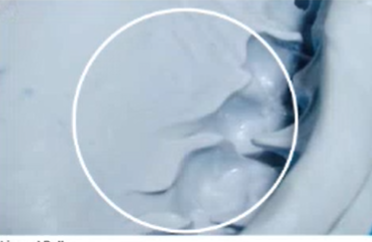

A

Hydrogen Evolution voids

Caused if manufacturer does not use a platinum catalyst - creates hydrogen gas instead of silica